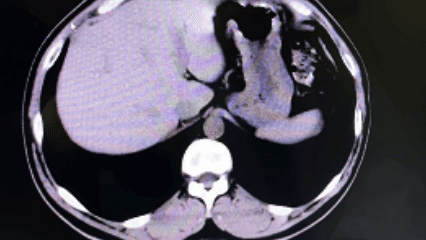

图片

在与患者及家属进行充分沟通,并获得手术同意后,医疗团队为患者实施了“经皮肾镜下右肾结石碎石取石术+经尿道输尿管支架管置入术”。术中,医生顺利穿刺、碎石,成功清除了困扰患者的结石;麻醉医生全程严密监护,确保生命体征平稳;护理团队默契配合,为手术的顺利进行提供了坚实保障。